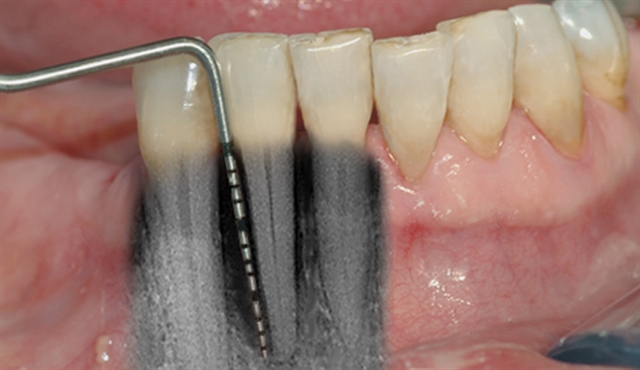

En undersøkelse med lommeregistrering avdekker likevel et omfattende bentap ved den ene tannen.

Instrumentet er her lagt utenfor tannkjøttet for å vise hvor stort festetapet egentlig er.